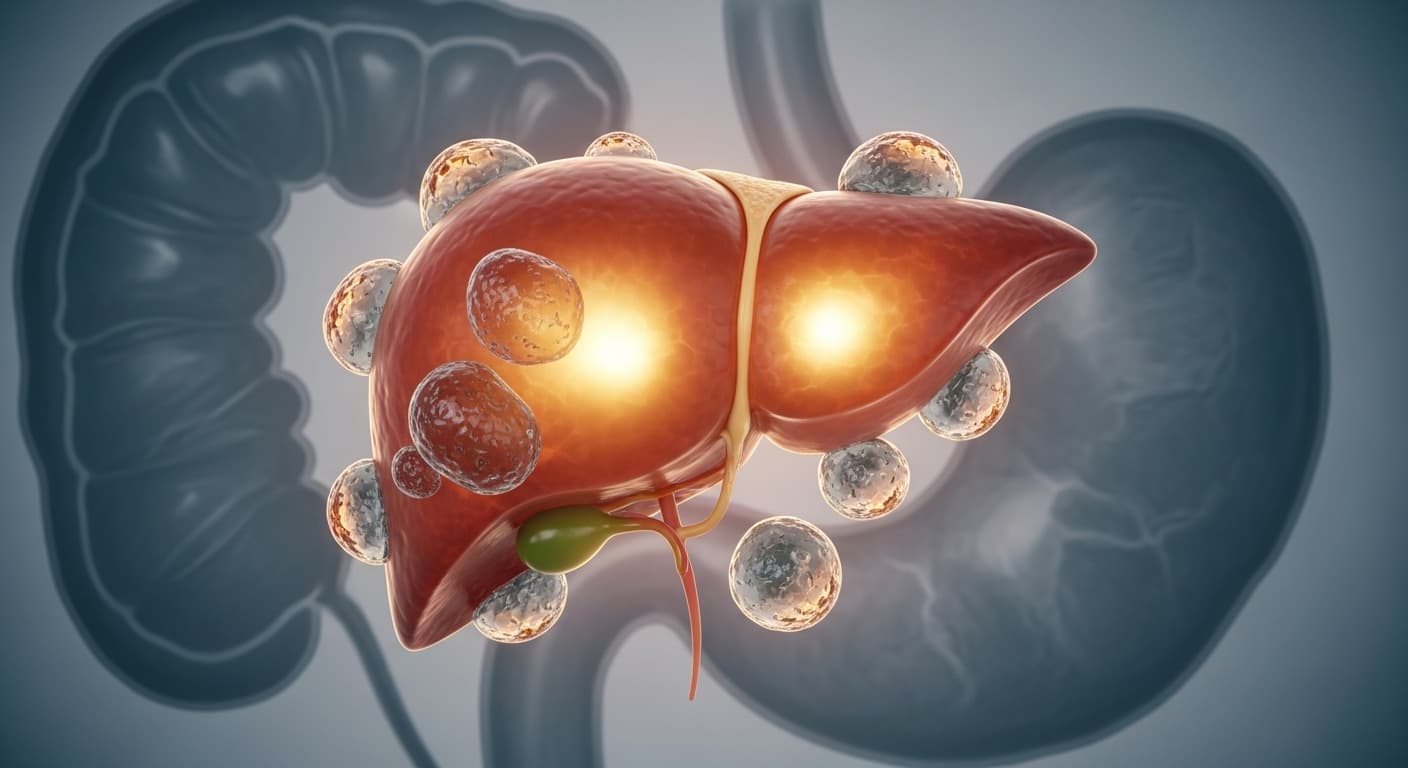

동의보감에서 말하는 '차고 서늘한 성질'과 '습담' 이야기가 어딘가 낯설게 들릴 수도 있지만, 현대 의학으로 풀어보면 깜짝 놀랄 만큼 정확한 통찰이 숨어있답니다. 바로 과일에 풍부한 '과당(Fructose)' 이야기예요. 과당은 이름 그대로 과일에 들어있는 자연 설탕이지만, 일반 설탕(자당)이나 포도당과는 우리 몸에서 처리되는 방식이 아주 달라요. 이 특별한 처리 방식이 다이어터들에게 예상치 못한 독이 될 수 있죠. 😱 포도당은 우리 몸의 모든 세포에서 에너지원으로 사용될 수 있고, 혈당을 직접 올려 인슐린 분비를 자극해요. 인슐린은 에너지를 세포로 이동시키고 남은 에너지를 저장하게 하죠. 그런데 과당은 주로 '간'에서만 대사됩니다. 췌장에서 인슐린을 거의 분비하지 않아, 뇌가 '배부르다'는 신호를 잘 받지 못하게 됩니다. 그래서 과일을 아무리 많이 먹어도 포만감을 느끼기 어렵고, 계속 먹고 싶은 충동이 들 수 있어요. 문제는 간이 과당을 너무 많이 받게 되면, 처리 능력을 초과하게 된다는 점입니다. 간은 과도한 과당을 에너지로 쓰지 못하고 '지방'으로 바꿔버려요. 이를 '신생 지방 합성(De Novo Lipogenesis, DNL)'이라고 하는데, 이 과정에서 만들어진 지방은 간에 쌓여 '비알코올성 지방간'을 유발하고, 더 나아가 뱃속 깊숙이 내장지방으로 축적되기도 합니다. 내장지방은 단순히 보기 싫은 살이 아니라, 염증 물질과 호르몬을 분비해 인슐린 저항성을 높이는 주범이에요. 인슐린 저항성이 생기면 몸이 인슐린에 둔감해져서, 혈액 속 포도당이 세포로 잘 들어가지 못하고 혈당이 높아지게 됩니다. 췌장은 더 많은 인슐린을 분비하려 애쓰고, 이 과도한 인슐린은 또다시 지방 축적을 촉진하는 악순환을 만들게 되는 거죠. 🔄 또한, 과당 섭취는 식욕 조절 호르몬에도 영향을 미쳐요. 과당은 식욕 억제 호르몬인 렙틴(Leptin)의 작용을 방해하고, 식욕 촉진 호르몬인 그렐린(Ghrelin) 수치를 정상적으로 낮추지 못하게 하여 지속적인 허기와 식탐을 유발할 수 있습니다. 마치 동의보감이 말하는 '습담'이 몸에 쌓여 대사를 방해하는 것처럼, 과당은 현대인의 몸속에서 지방을 쌓고 대사를 혼란스럽게 만드는 주범이 될 수 있다는 의미예요. 물론 과일 자체는 비타민, 미네랄, 식이섬유가 풍부한 건강식품입니다. 하지만 '과유불급'이라는 말처럼, 과도한 섭취는 독이 될 수 있어요. 특히 당도가 높은 과일이나 과일 주스 형태로 섭취할 때는 주의가 필요합니다. 건강한 다이어트를 위해서는 과일 섭취량과 방법을 현명하게 조절하는 지혜가 꼭 필요하다는 걸 현대 의학이 다시 한번 강조하는 것이죠. 우리 몸을 사랑하는 만큼, 과당의 이면도 꼭 기억해주길 바라요! 🍓🍎🍊